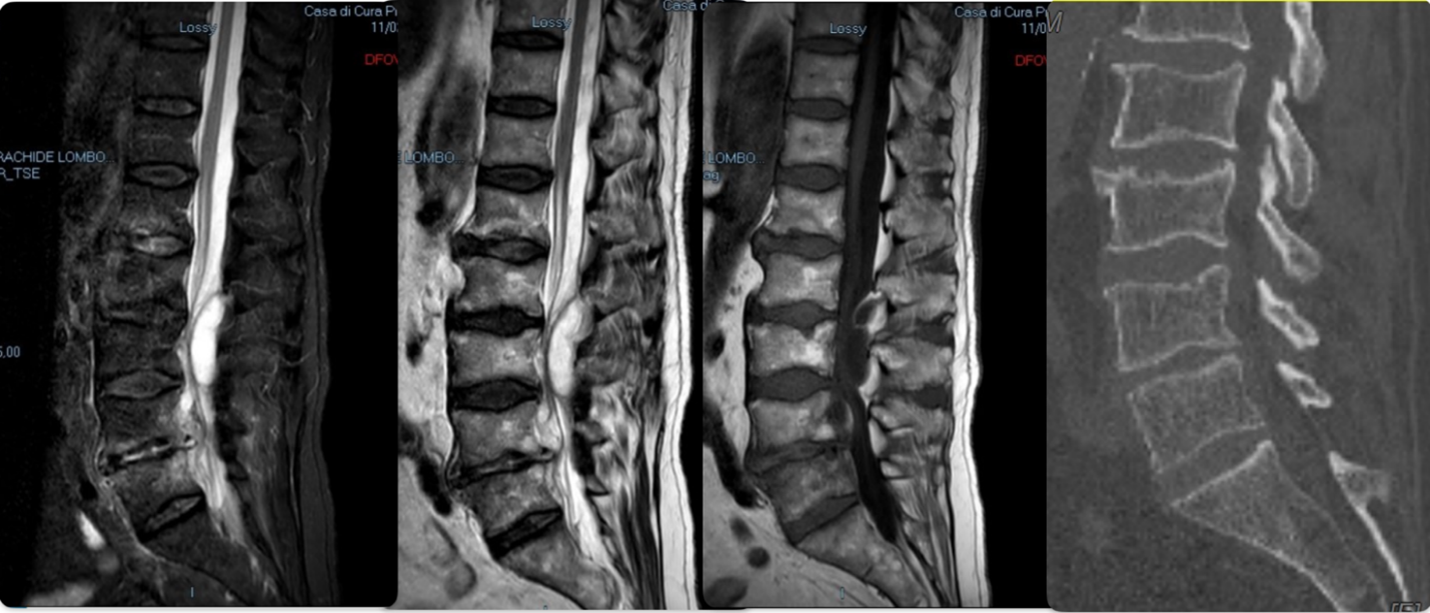

At medical examination he had no neurological deficits, only important limitation of lower limbs movements caused by pain exacerbation, in fact he was already forced to bed rest for at least a week at home. A single episode of high temperature detection was referred, a total spine MRI without iv contrast, conducted in another facility just a few days before, was available (Figure.1).

It showed a formation in the posterior epidural space at L2-L3 level in continuity with a less visible one localized in the anterior epidural space below, at L3-L4 level. Here, the adjacent endplates (L3, L4) showed significant high signal, caused by bone marrow edema without further signs of vertebral involvement.

Figure 1: A. MRI FLAIR sequence- high signal massive posterior epidural formation L2-L3 with visible outlines, high signal smaller formation in the anterior epidural space L3-L4 with more blurred outlines.

B. MRI T2 sequence- Confirmation of the two epidural collections (hyperintense signal). High signal of lumbar vertebral plates.

C. MRI T1 sequence- recognizable anterior epidural formation, barely visible the upper side of the posterior formation (hypointense signal). High signal of lumbar vertebral plates, especially L3.

The clinical symptoms associated with these radiological features were all suggestive for a case of spondylodiscitis, despite the lack of an impressive bone implication.

According to spondylodiscitis guidelines (IDSA-2015)5 and EANS Spine Section Delphi consensus recommendations (2024)3, at the admission in our department the patient underwent chest X-ray, which resulted normal, CT total spine scan, that was negative for vertebral collapse or massive endplates erosion (Figure.1). Blood and urine cultures were taken and came out as negative after a standard period of 5 and 2 days, respectively.